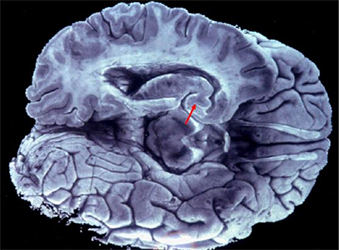

[5] El movimiento desencadena un mecanismo oculto de 'limpieza cerebral', según un estudio de la Universidad Estatal de Pensilvania (Penn State) realizado en ratones. l aplicar una ligera presión en los abdominales de ratones anestesiados, los investigadores confirmaron que esta era la fuente del desplazamiento cerebral. Con tomografías microcomputarizadas que utilizan rayos X  los científicos reconstruyeron virtualelmente en 3D las estructuras internas, revelarondo la red de venas que conforman una  'bomba' entre la cavidad abdominal, la médula espinal y el cerebro. Esta bomba fiunciona de manera parecida a una esponja, posiblemente en todos los mamíferos, subiendo el líquido cefalorraquídeo por la mádula espinal y penetran el cerebro para regarlo por esa red de de venas. /2026/05/10 /Science Alert. Fuente: Nature Neuroscience. Imagen: Observan en ratones cómo el fluido cerebroespinal con el movimiento llega hasta el cerebro regandolo por la red venosa. /C. Spenser Carborg et al. /nature Neuroscience.